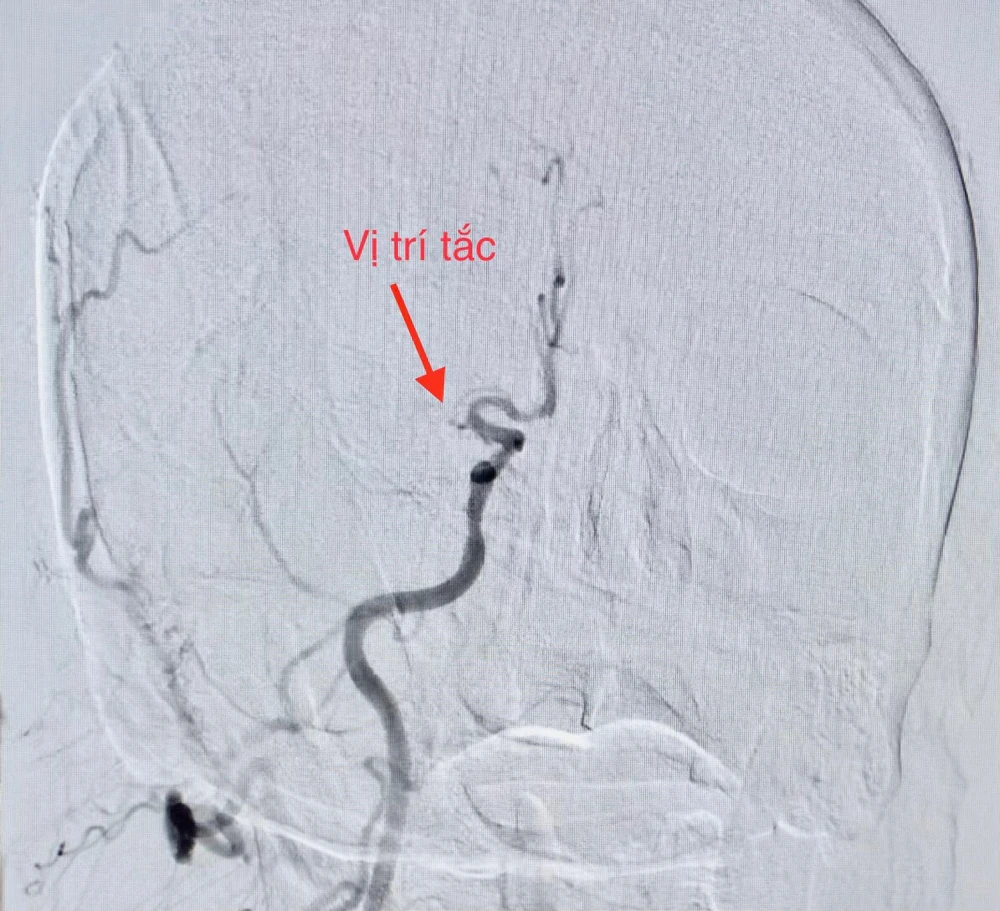

Hình ảnh mạch vành và não bệnh nhân bị tắc dẫn đến nhồi máu cơ tim và đột quỵ. Ảnh: BVCC |

Sau đó, êkíp tiếp tục can thiệp mạch não chụp kiểm tra phát hiện tắc động mạch não giữa bên phải, thủ thuật lấy huyết khối tái thông mạch máu bị tắc.